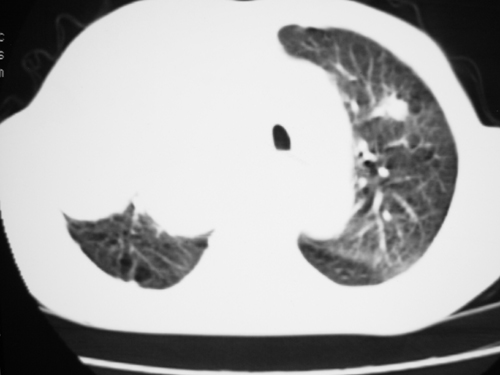

以下是引用yangyudong333在2008-4-29 5:46:00的发言:[br]1左上叶结节呈分叶状,边缘毛刺,考虑肺癌并纵隔淋巴结转移可能性大,结核待排,[br] [br]2右侧多发包裹性胸腔积液

以下是引用zsl6918在2008-4-29 9:15:00的发言:[br]右侧包裹性积液穿刺术后改变,肺内多发结节不除外转移可能。建议查胸水,问病史。